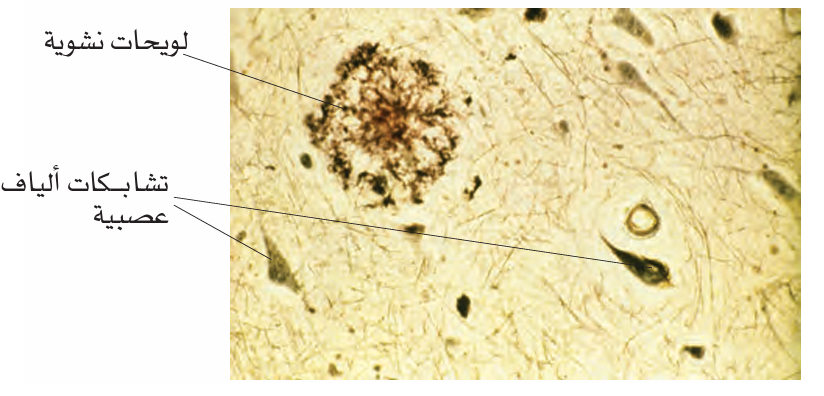

رؤية مجهرية للغدة الدرقية (Thyroid Gland)

تُظهر الرؤية المجهرية للغدة الدرقية جُريبات (Follicles) تشبه كرات غولف غير مكتملة الاستدارة. وتعود التعرجات الظاهرة على سطح هذه الجريبات إلى الخلايا الجُريبية (Follicular Cells)، وهي الخلايا المسؤولة عن إنتاج الهرمونات الدرقية، مثل T₄ و T₃وإفرازها إلى الشعيرات الدموية المجاورة (Capillaries). أما المادة الموجودة داخل الجريبات، وهي الغُرواني (Colloid)، فتتكون أساسًا من الثيروغلوبيولين (Thyroglobulin)، وتعمل كمخزون لهرمونات الغدة الدرقية قبل إفرازها.